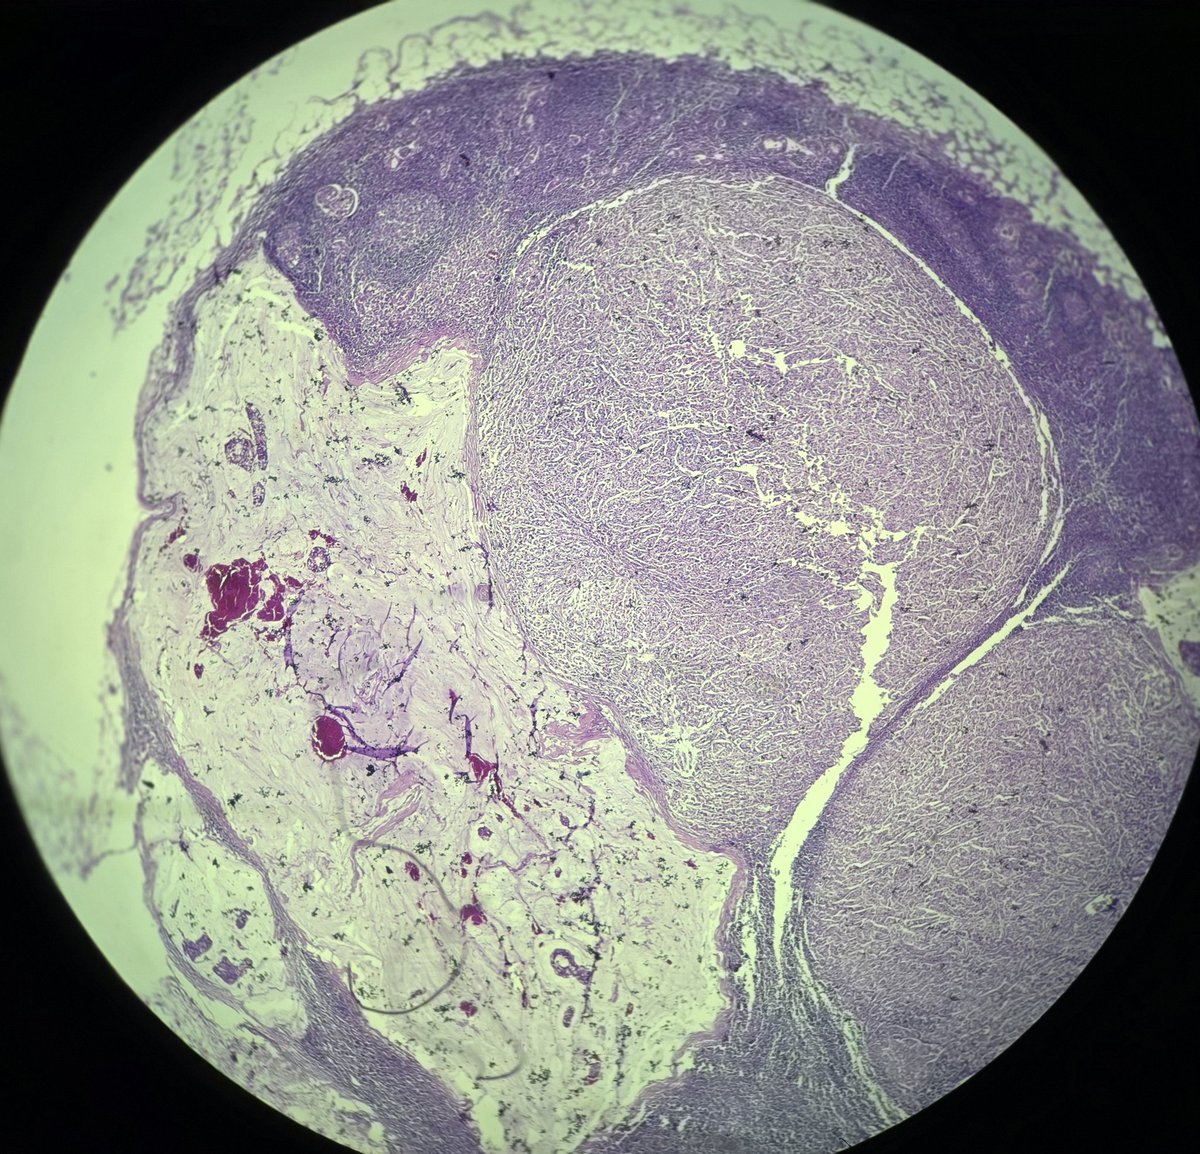

13 yrs old boy with gradually enlarging cervical lymphadenopathy. A case of metastatic lymphoepithelial carcinoma lurking in nasopharynx. #pathology #ENTPath